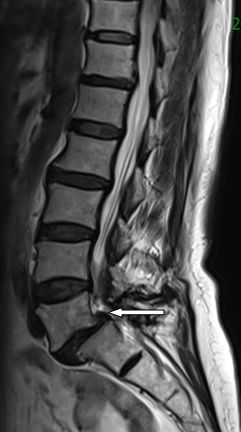

在完善了相关检查后刘阿姨被确诊为腰椎滑脱症—腰5椎体II度向前滑脱。

腰5椎体2度

向前滑脱

脊髓受压变形